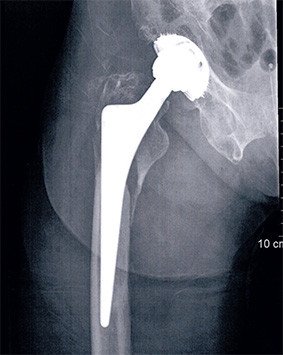

Oberschenkelbruch auf Prothesenhöhe

Die 77-jährige Patientin zog sich bei einem Sturz einen Bruch des Oberschenkels auf Prothesenhöhe zu.

Bei der Operation zeigte sich eine relativ starke Zertrümmerung des Knochens oberhalb des Bruches. Der Prothesenschaft selbst war durch diesen Bruch nicht mehr fest, sondern gelockert. Der Schaft musste entfernt und durch einen neuen ersetzt werden. Wir haben einen zementierten Schaft gewählt, der hier den Vorteil hat, dass die Trümmer sich besser an den Knochenzement anmodellieren lassen. Die diversen Fragmente wurden durch Schrauben und Drähte stabil fixiert. Während der Operation zeigte sich, dass die Hüfte instabil war, weshalb auch die Pfanne ausgewechselt wurde.

Der postoperative Verlauf war unauffällig, die Patientin hat sich gut vom Eingriff erholt. Aktuell ist sie beschwerdefrei und auch stockfrei gut gehfähig. Die Patientin ist mit dem Resultat zufrieden.